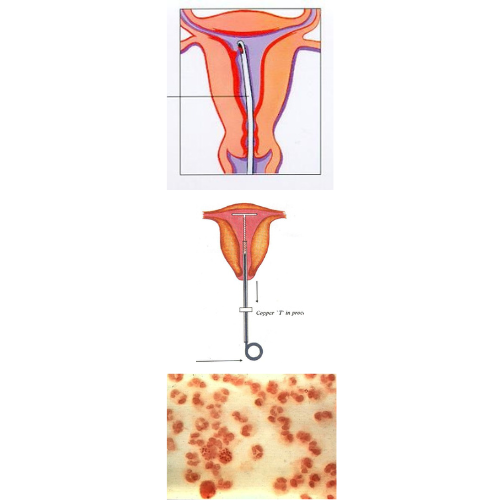

Infective Organisms commonly belong to Gram negative and gram positive bacilli. For example E.Coli, Neisseria gonorrhoeae (a), Chlamydia trachomatis, Klebsiella, pseudomonas, Staphylococcus etc.,

The other non bacterial pathogens are Mycoplasma hominis, Ureaplasma Urealyticum, Actinomyces israelii, Mycobacterium tuberculosis and virus like Herpes simplex (HV-2)